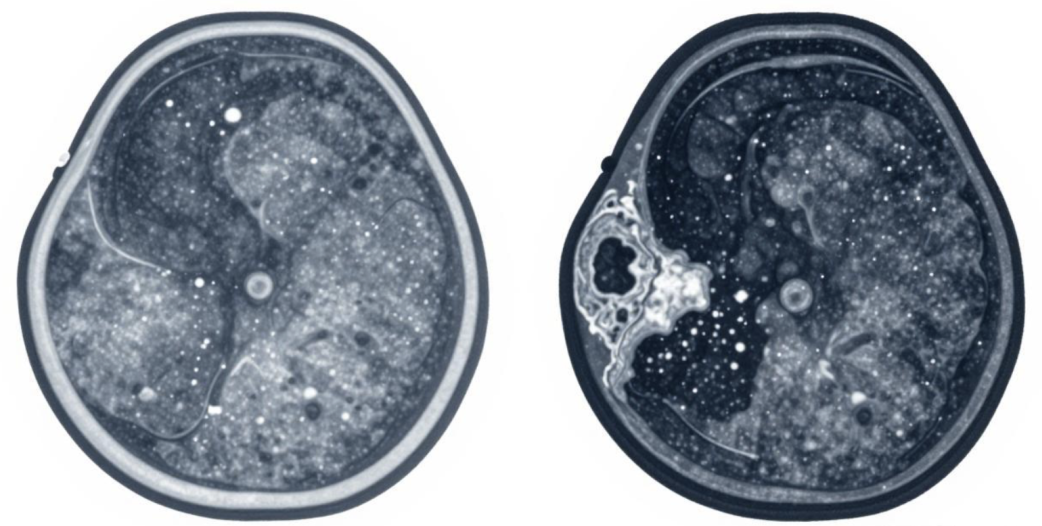

钙化是乳腺结节常见的表现,不同形态的钙化,良恶性差异很大。良性结节的钙化,多是粗大、分散的,比如大颗粒钙化,稳定性强,基本没有风险。而恶性倾向的钙化,常是细小、密集的泥沙样或分枝状钙化,聚集在一起,这种钙化是恶性病变的重要提示,需要重点关注。